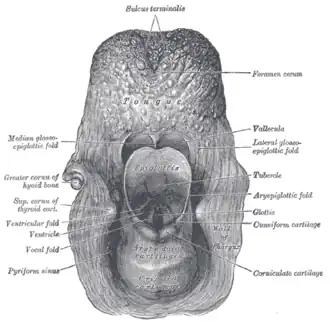

Additional images

Coronal section of larynx and upper part of trachea.

Coronal section of larynx and upper part of trachea. -

The entrance to the larynx, viewed from behind.

The entrance to the larynx, viewed from behind. -